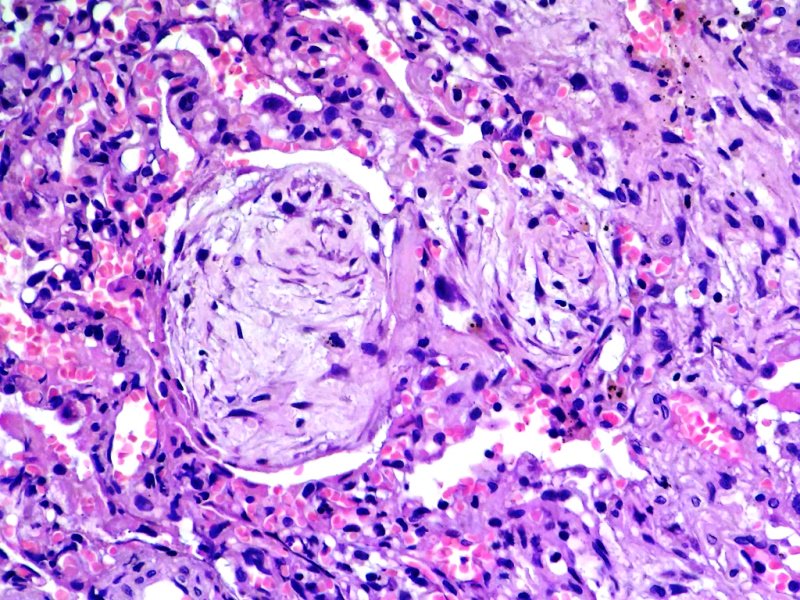

Tumor en conducto de médula espinal lumbar. Ependimoma tanicítico. Tinción HE.

Anapat tweet mediaAnapat tweet mediaAnapat tweet media